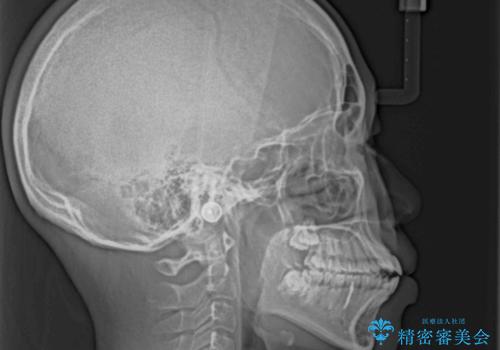

舌の突出癖により上下前歯は接触できず、更には前方に押し出されて出っ歯になっている状態でした。

上下左右の第一小臼歯4本を抜歯し、ワイヤー装置での抜歯矯正を行っていくのですが、原因である舌の突出癖を改善しないことには治療がうまく進められないため、舌のトレーニングを徹底するよう指導していくこととしました。

当初は舌のトレーニングがうまくできていなかったのですが、途中から奏効し、非常に短い期間で治療を終えることができました。